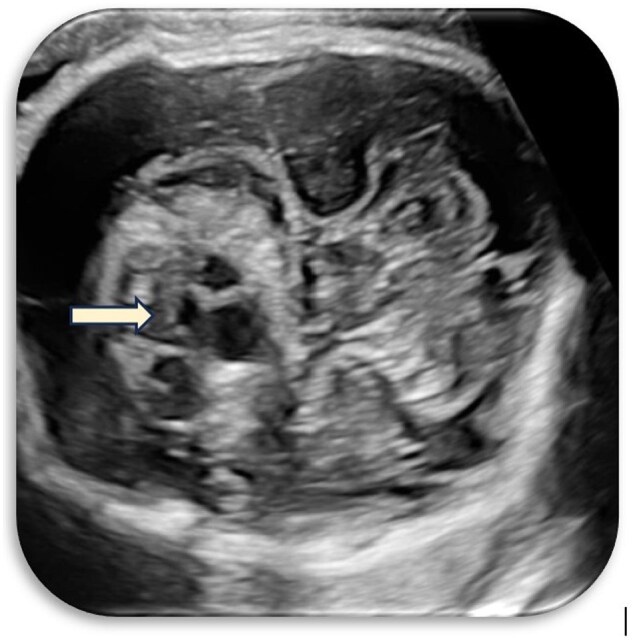

Unravelling fetal enigmas: a case of suprasellar lesion.